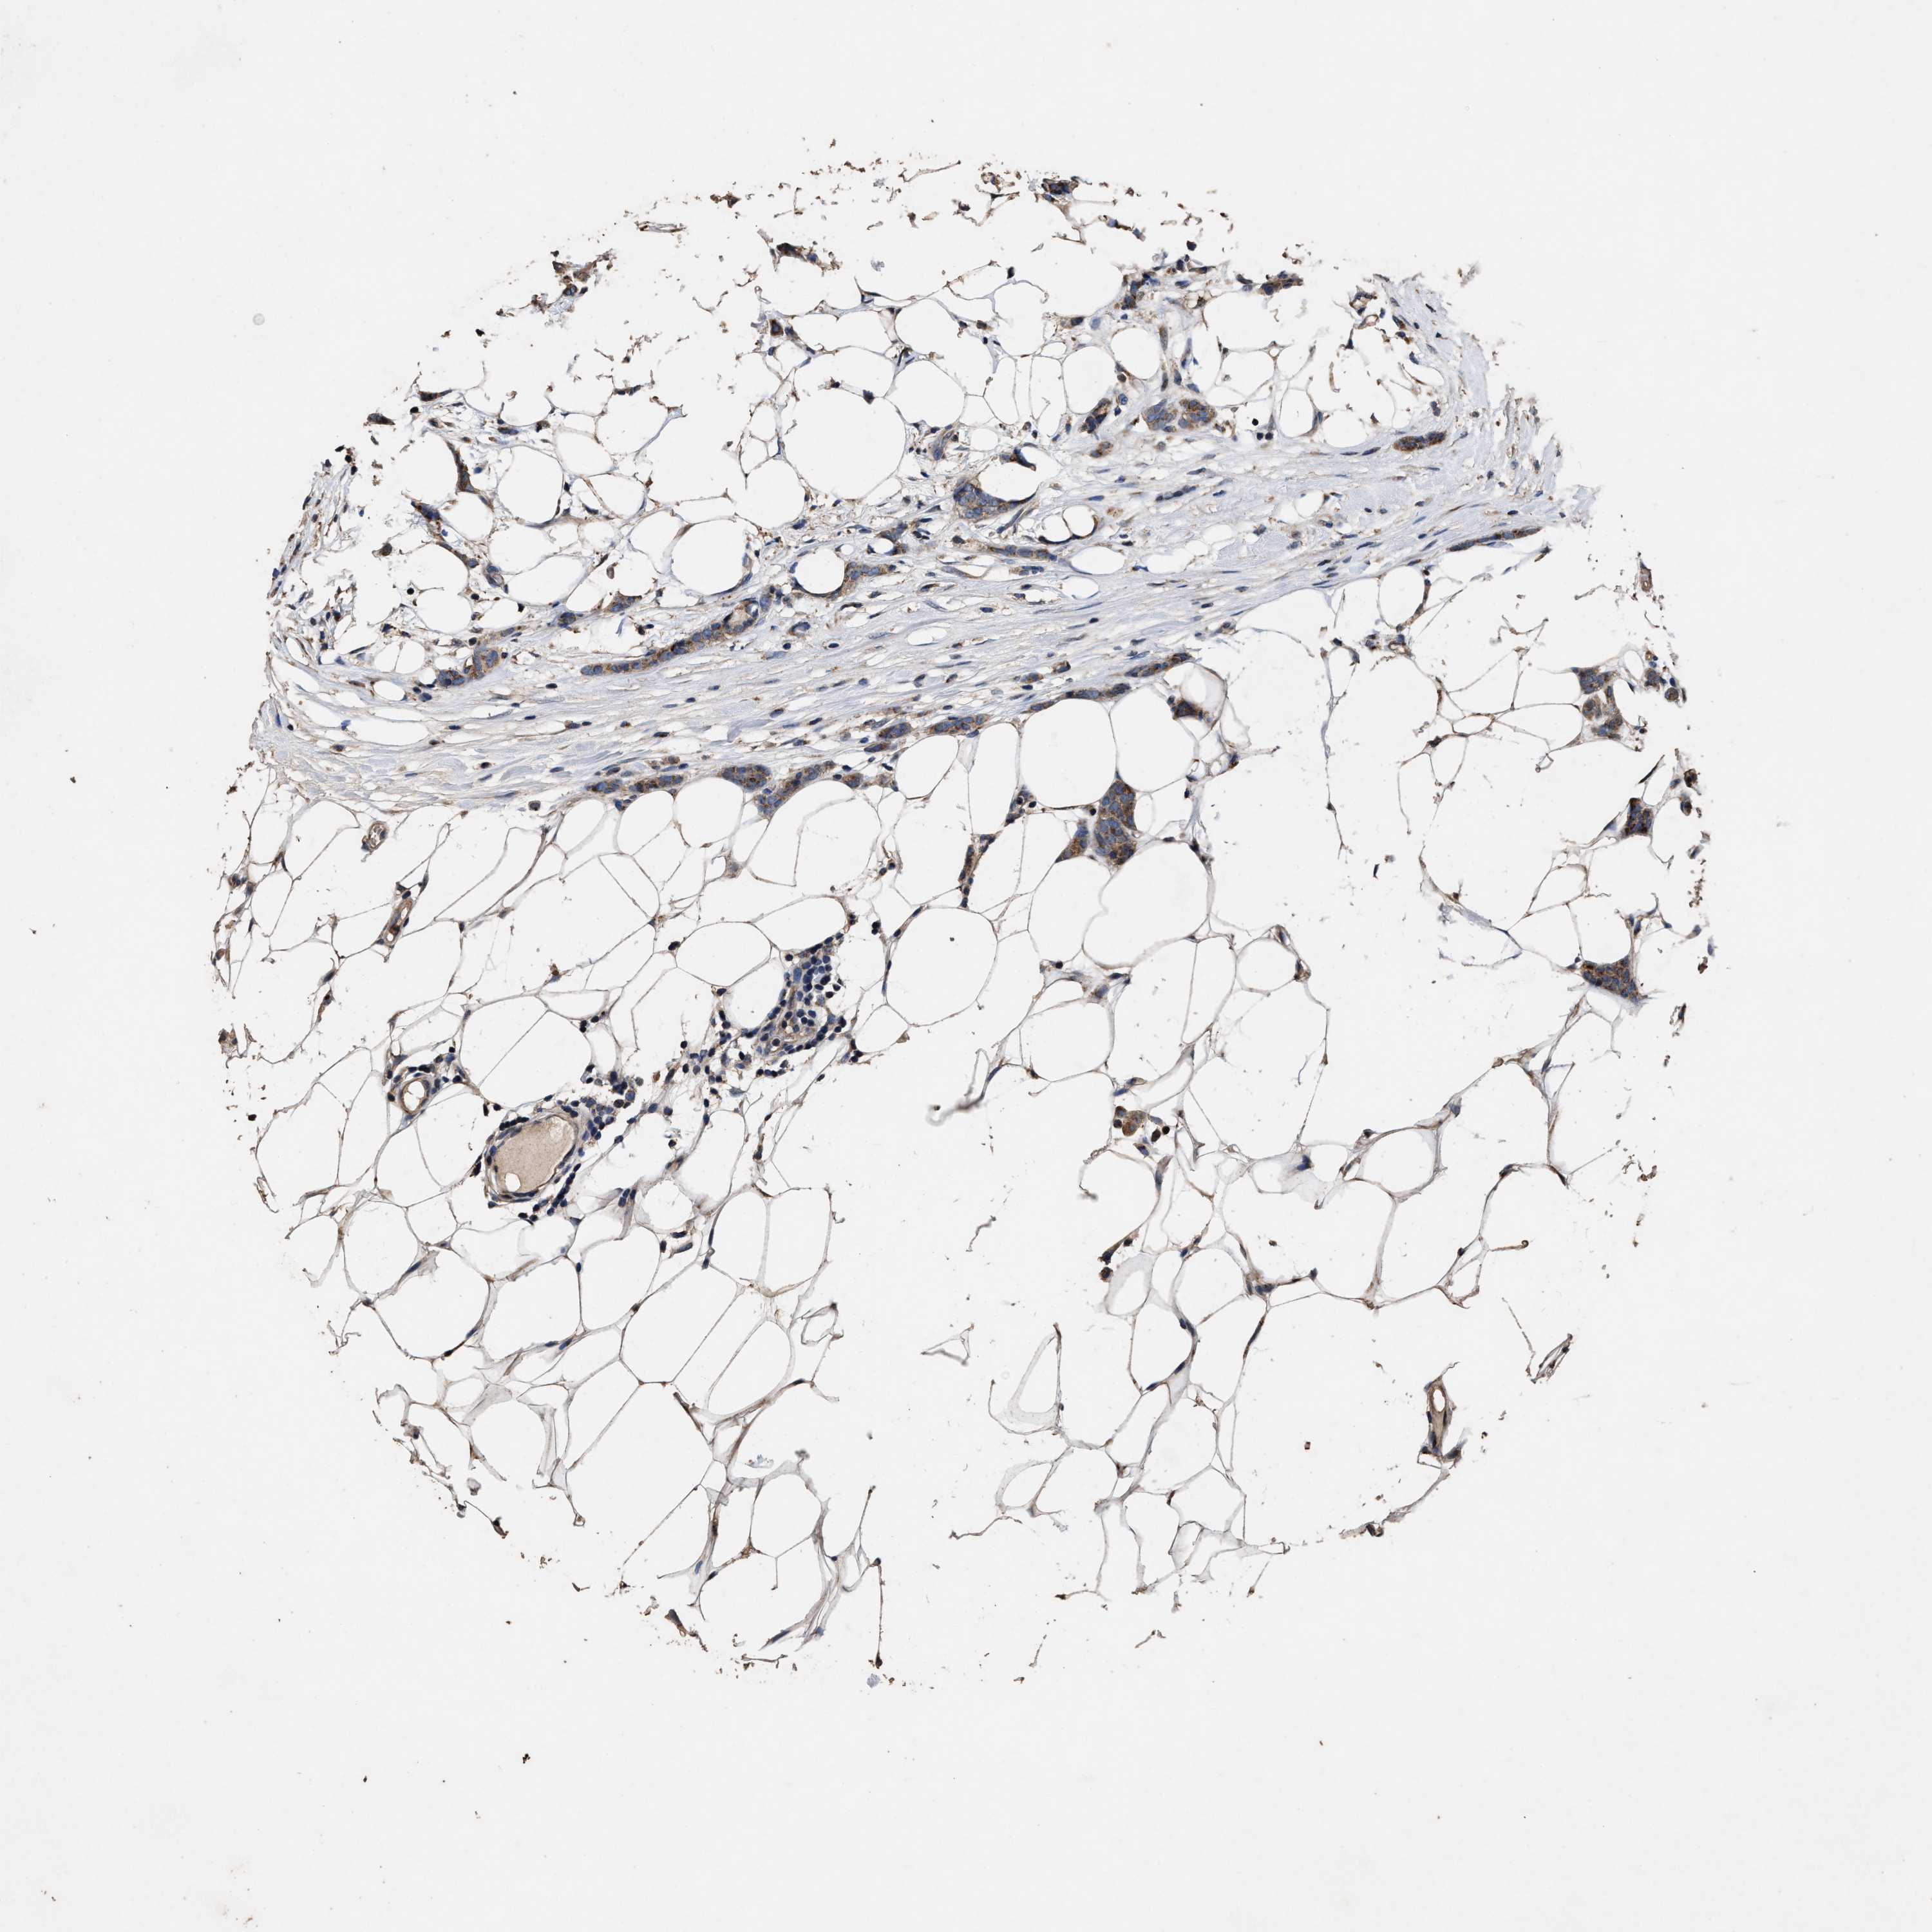

CANCER BREAST CANCER Show tissue menu

BRCA TCGA BRCA VALIDATION PROTEIN EXPRESSION

Breast cancer

Human cancer